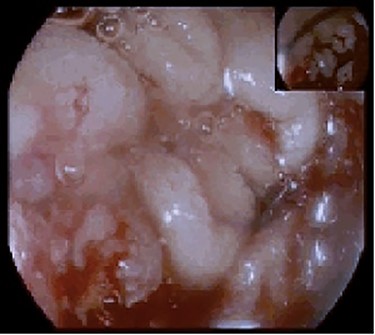

The patient was also being studied in our outpatient clinic for a symptomatic iron deficiency anaemia and had an upper gastrointestinal (GI) endoscopy performed the day before attending the ED. The endoscopy revealed a proliferative and ulcerated lesion involving the transition between the second and third portions of the duodenum (D2–D3; Fig. 1).

Upper endoscopy showing an ulcerative and friable duodenal lesion.

To this day, despite direct invasion being quite common, there have been very few reports of duodenal metastasis of malignancies originated in distant organs. Lung, renal, melanoma and colorectal cancer have sporadic reports of duodenal involvement [8, 9]. When identified on endoscopy, they frequently present as ulcerated lesions that can cause GI bleeding or gastric outlet obstruction. This finding is consistent with the endoscopy’s macroscopic description of the duodenal lesion and our patient’s clinical presentation. Immunohistochemistry provided the diagnosis after confirming its non-lower GI tract origin and gynaecologic related epithelial structure (positive for cytokeratin 7, negative CDX2 and positive PAX8 immunostaining) [3, 10].